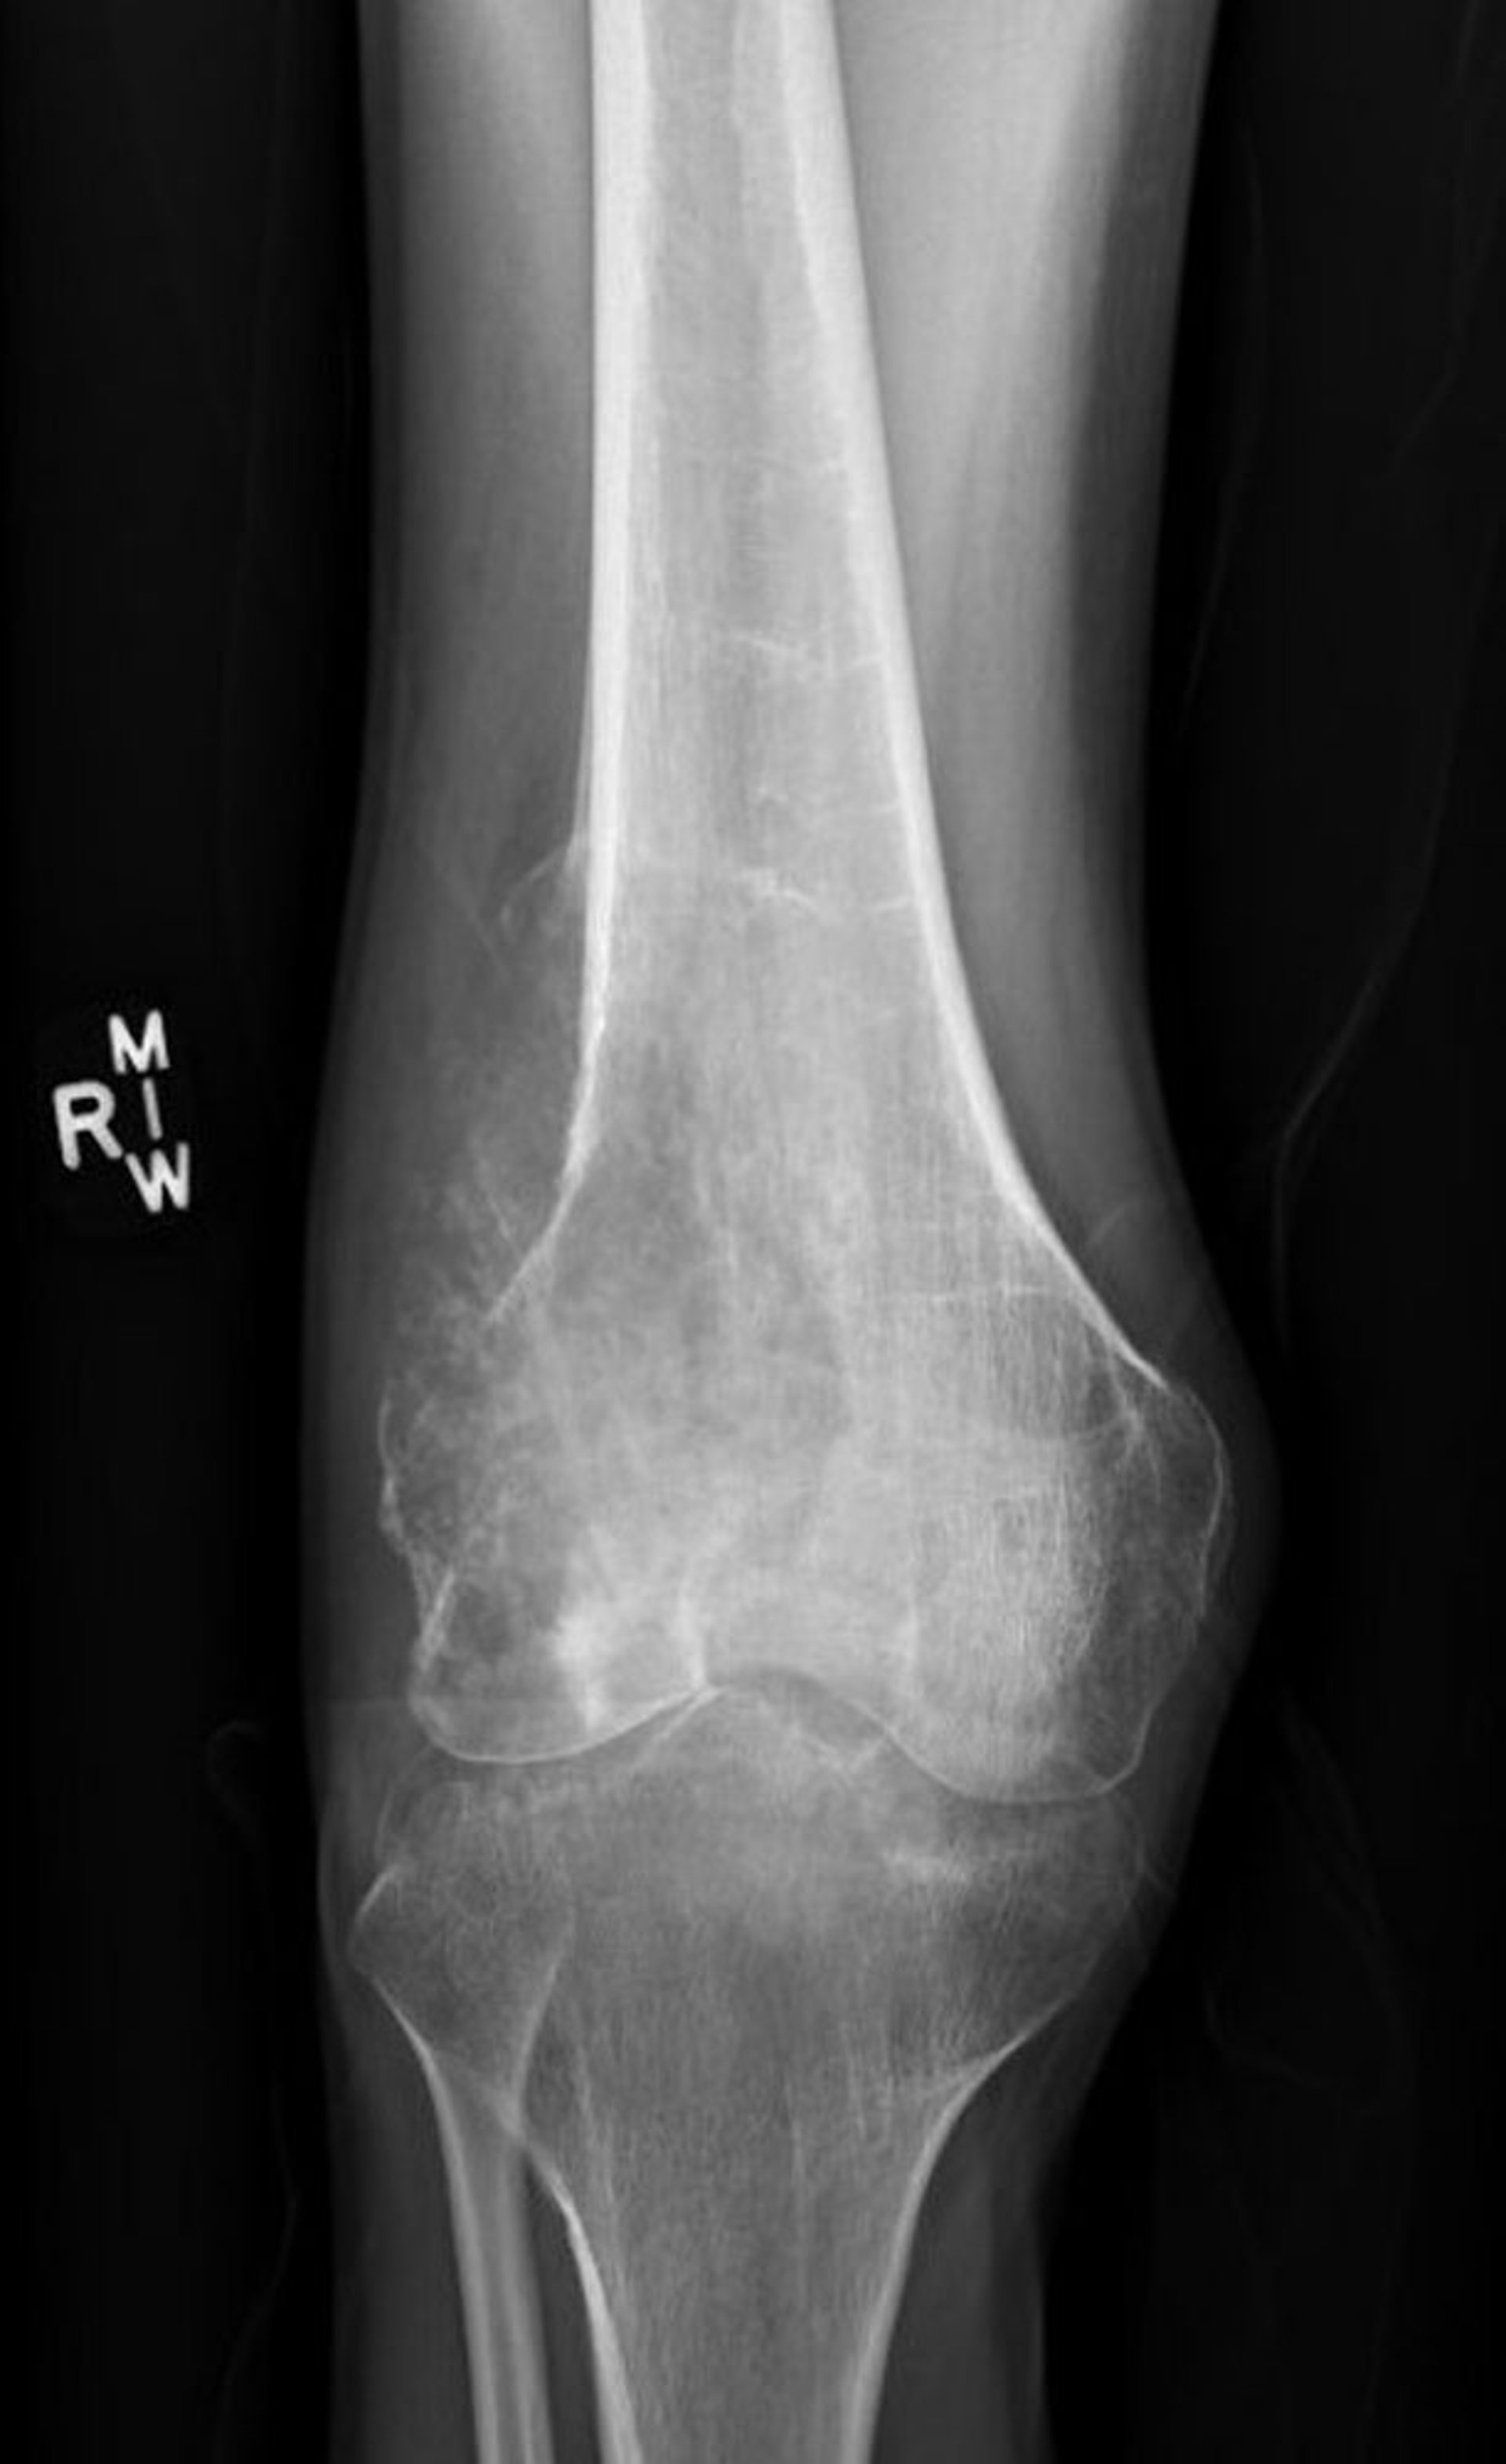

Osteossarcoma

Esta radiografia do joelho mostra um osteossarcoma destrutivo no fêmur acima do joelho com uma aparência lítica destrutiva e um clássico triângulo de Codman mostrando elevação periosteal patológica.

Image courtesy of Lukas Nystrom, MD.